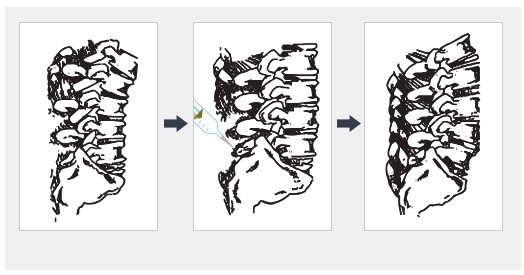

하지만 이때 관리가 제대로 이루어지지 않고 통증을 방치하게 된다면

근육통뿐만 아니라 목 관절의 변형과 함께 찾아오는 관절의 퇴행성변화로

목 통증과 함께 신경을 압박하면서 목을 움직이기 힘든 통증과 함께

팔이 저리거나 두통과 같은 신경통이 발생할 수 있습니다.

후관절내측지차단술!

척추 후 관절을 담당하는 신경을 치료하는 주사치료법으로

척추 경막 외강에 주사하는 기존 방법과 다르게 컴퓨터 영상 장치를

이용해 통증의 원인 부위 관절에 바늘을 삽입하여 주사 약물을

주입하는 치료방법입니다.